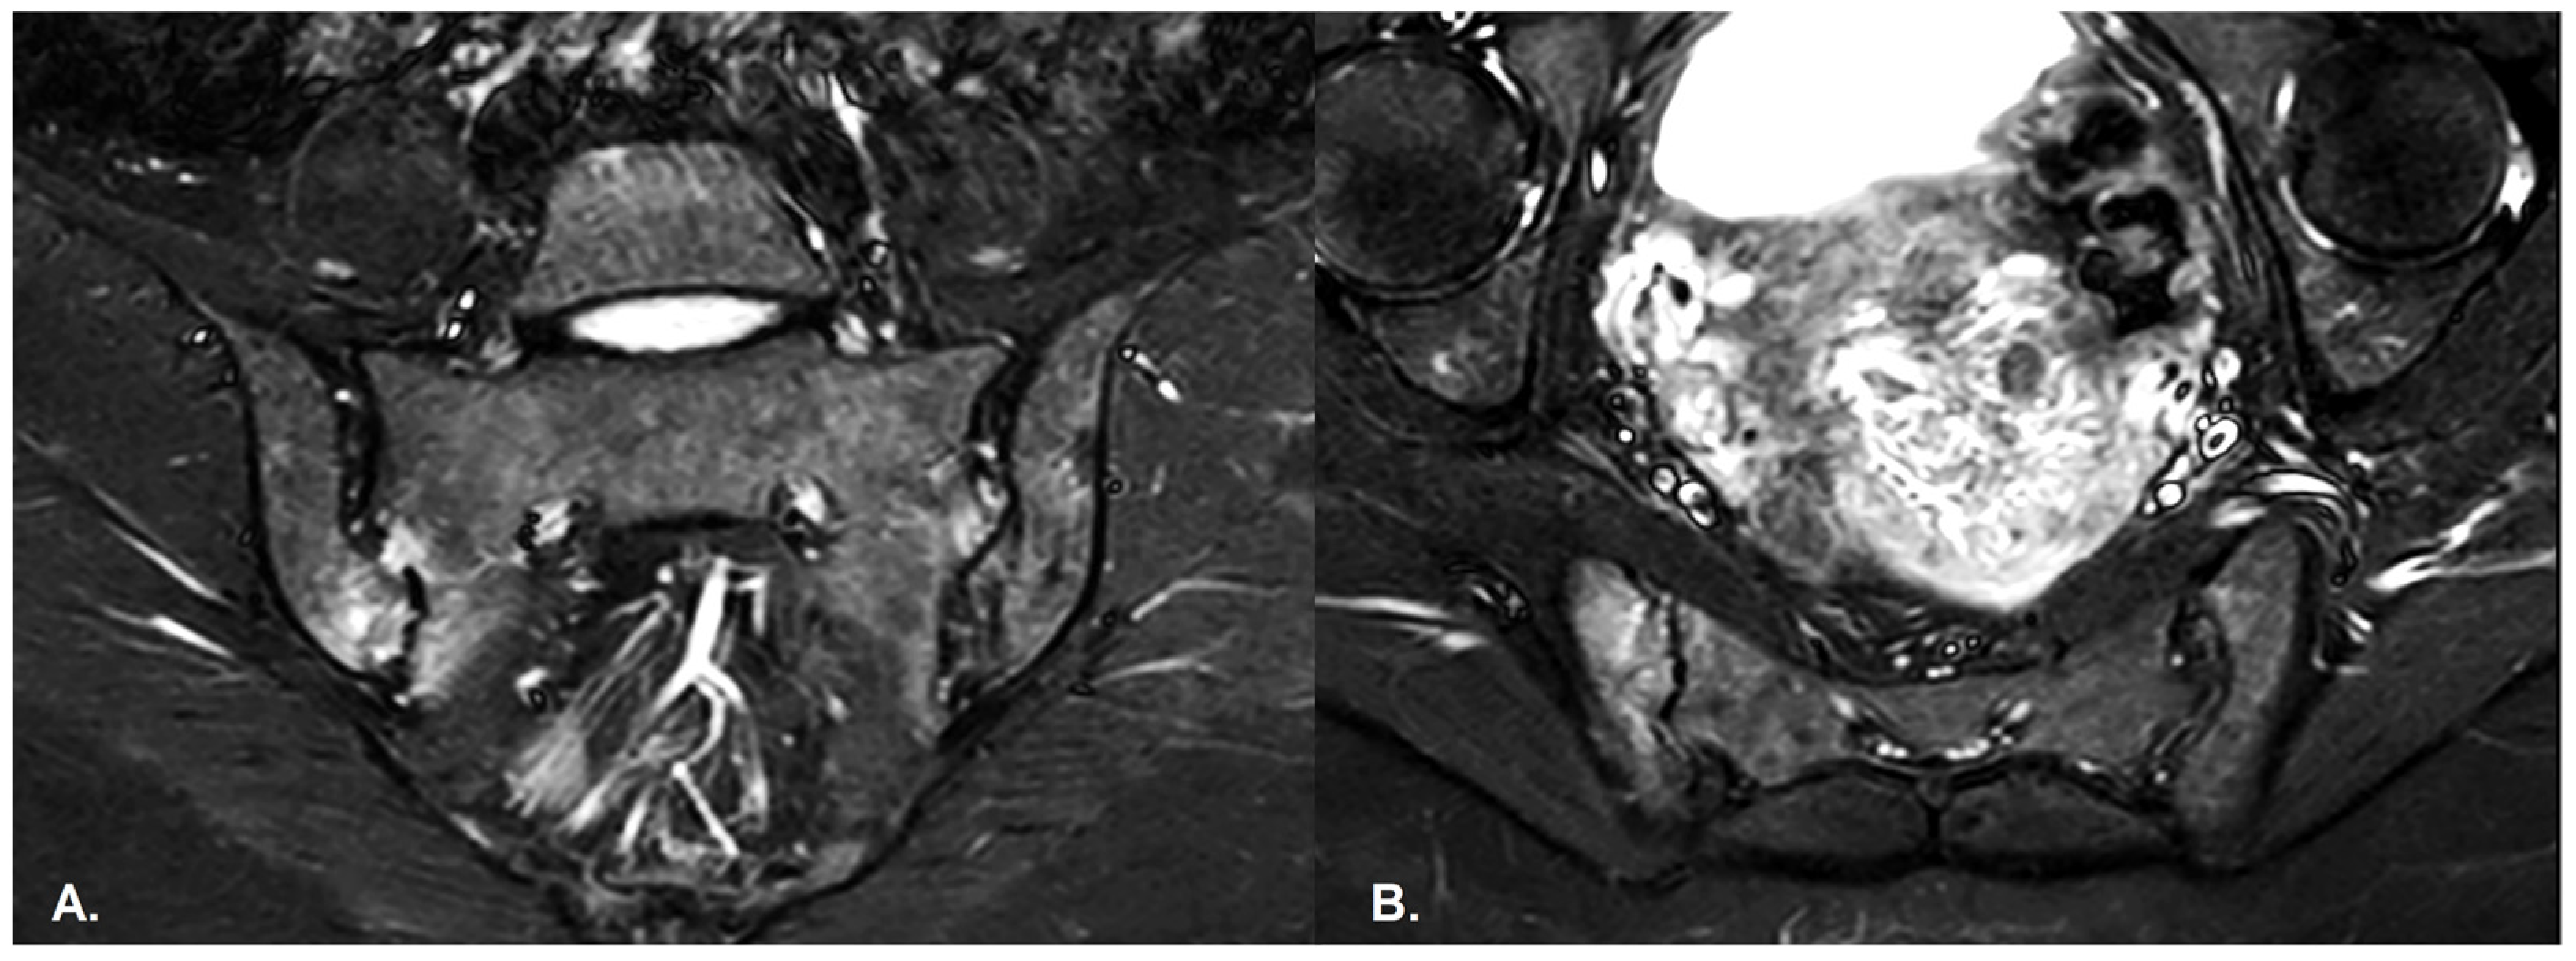

- BME is evident in low signal T1w, hyper signal T2w, STIR images and +C T1w Fat-Sat, similar to blood vessels and spinal fluid; the signal intensity is directly proportional to the inflammation activity. It is usually located periarticular to or on the subchondral bone surfaces and it is an indicator of disease activity (Figure 4) [65].

- Capsular inflammation—increased signal on T2w GRE and STIR sequences.

- Enthesitis—entheses are normally seen as hypointense structures, whereas inflammation leads to an increase in signal; best visualized on T2w Fat-Sat and STIR sequences. There are similar findings in both PsA and SpA [65].

- Erosions–initially focal, later they will converge and will have a pseudo-enlargement aspect of the sacroiliac joint. In T1w images there is a loss of cortical bone signal (normally hypointense) and bone marrow fat (normally hyperintense).

- Sclerosis—better visualized on an X-ray or CT scan; a subchondral or periarticular area with a low signal compared to normal bone marrow on T1, T1FS (SPIR), and STIR sequences (Figure 5).Slight: <25% of the subcortical bone area.Moderate: 25% to <50% of the subcortical bone area.Severe: >50% of the subcortical bone area [29].